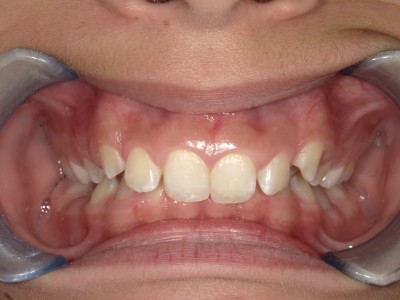

1-26 maand Volledig vast onderkaak + Transforce onderkaak